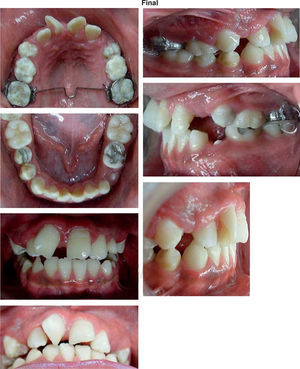

RESULTADOS DEL TRATAMIENTOLa mordida cruzada anterior del paciente fue eliminada y las radiografías y trazos cefalométricos de Steiner, Jarabak y Ricketts fueron repetidos al término de la fase ortopédica.

La sobremordida horizontal de -2mm inicio y 2mm posterior se incrementó 4mm obteniéndose una sobremordida vertical de 2mm.

La sobreposición de los trazos cefalométricos ilustran los cambios del paciente (Figuras 8 a 13 y Cuadro II).